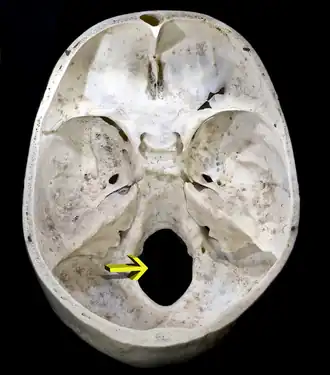

![]() Superficie interior de la base del cráneo. El agujero señalado por la flecha es el foramen magno. | ||

Foramen magnum, también conocido como agujero magno o agujero occipital, es el nombre del orificio mayor situado en la parte posteroinferior del cráneo (base del cráneo, piso témporo occipital), a través del cual se establece la continuidad del sistema nervioso central hacia el raquis.